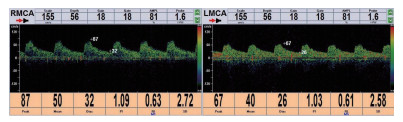

1.2 TCD检查采用中国深圳德力凯公司的超声经颅多普勒血流分析仪(EMS-9A),所有患者分别在24 h之内和第3天进行TCD检查,检测时暂停镇静药物。以2-MHz探头通过颞窗探测其两侧大脑中动脉,每一侧检测3次,取其最高值,将两侧最高值的平均数作为有效数据进行记录,检测内容包括平均血流速度(mean Velocity, Vm)、搏动指数(pulastility Index,PI)、阻力指数(resistivity index,RI)、收缩期峰值血流速度(peak systolic velocity,PSV)、舒张末期峰值血流速度(end diastolic velocity,EDV)等各项参数。其中一位患者第1天及第3天TCD检查图像见图 1。

| 图 1 脓毒症患者第1天和第3天TCD图像 Fig 1 TCD images of sepsis patients on day 1 and day 3 |